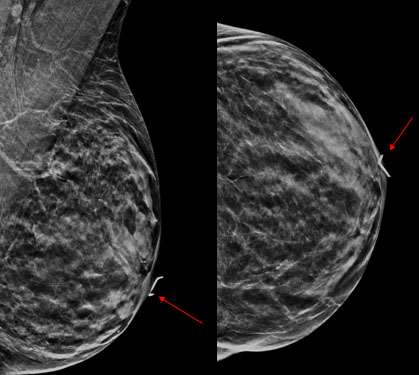

Case: Paget's Disease Figure 1

Figure 1: CC and MLO mammograms of the left breast. There is subtle skin thickening of the nipple and areola. An overlying sticker has been placed to denote the area of skin changes as indicated by the patient.